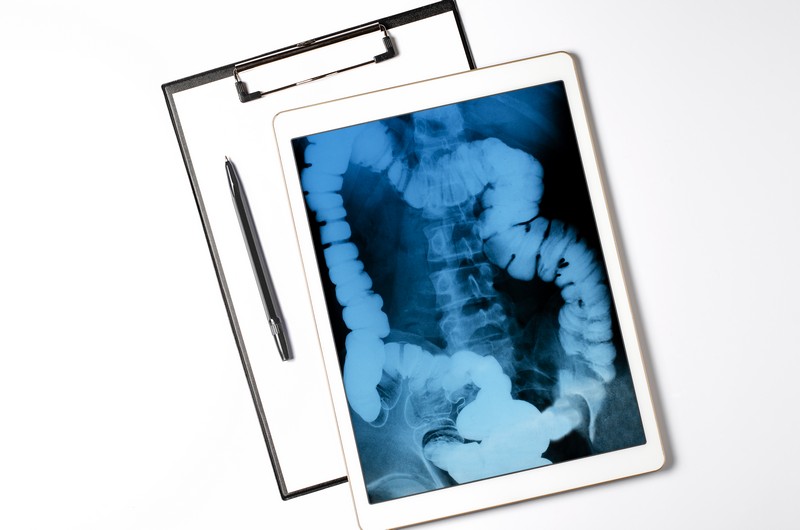

Диагностика канцероматоза брюшины— необходимая часть для выявления злокачественного процесса. Она представляет собой комплексные диагностические процедуры, которые помогают точно диагностировать метастазы в брюшной полости.

Комплексное применение разных способов диагностики позволяет точнее определить стадию поражения брюшины и составить эффективный план терапии.